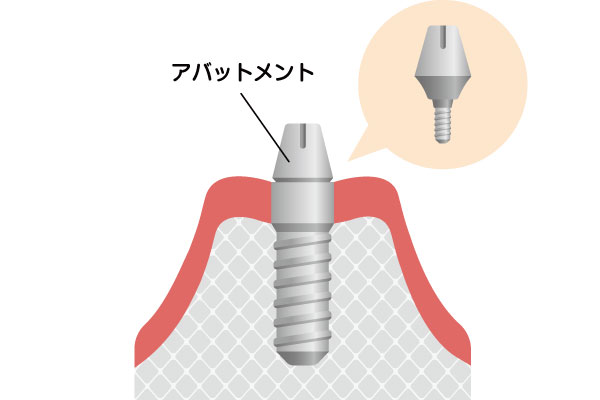

インプラント治療は、失った歯を補うために人工の歯根(歯の根っこ)をあごの骨に埋め込む治療法です。インプラント体は通常チタンでできており、チタンが骨と結合する性質があることから、強固で安定した基盤が作られ、その上にアバットメント(土台)を接続し、上部構造(人工歯)を装着します。これにより、見た目も自然で、機能的にも快適な歯を再建することができます。インプラントは自分の歯とほぼ同じように感じられ、他の歯への負担も最小限に抑えられます。

アバットメントの取り付け

インプラントがしっかりと骨に結合した後、人工歯を支えるためのアバットメント(人工歯の土台)をインプラントに取り付けます。この手術も局所麻酔で行い、比較的短時間で終了します。